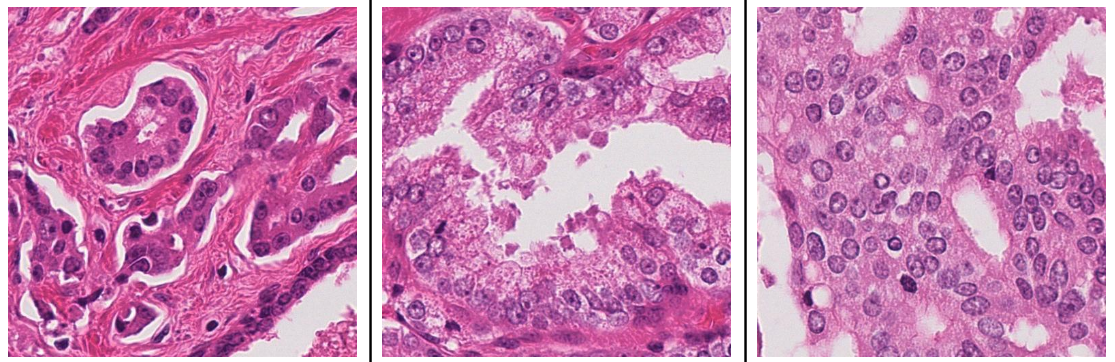

In addition, researchers have proposed various strategies to address imbalanced datasets. One approach involves using a weighted cross-entropy loss function during model training, adjusting class weights to balance class representation [3]. Another strategy combines data augmentation and resampling techniques, applying transformations like rotation and flipping to enhance dataset diversity and replicating images of underrepresented classes [2]. Some studies introduce novel algorithms, such as the focal loss function, which prioritizes minority class samples during training, and co-training approaches that leverage pseudo-labeled data [5, 6]. Evaluation metrics like the macro F1 score are also utilized to ensure fairness across all classes, alongside techniques like random patch sampling from whole slide images to manage large datasets [8]. Lastly, significant improvements have been made by increasing dataset size through extensive data augmentation [11]. To counteract the class imbalance present in our dataset, where each class has a differing number of samples, we utilized data augmentation methods to achieve a balanced class representation. Specifically, the dataset underwent rotations up to 10 degrees and height shifts of up to 10%, effectively increasing the number of instances for underrepresented classes. This augmentation strategy was crucial for preventing bias towards classes with larger sample sizes, ensuring a fair and balanced learning environment for the model. Figure 1 illustrates various examples of Gleason2019 annotations, showcasing different grades of severity.

Refer to caption

Figure 1: Examples of Gleason 2019 annotations. Left G3, middle G4, and right G5.